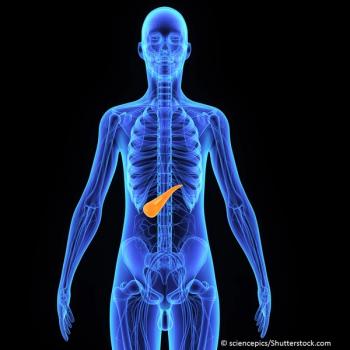

A presentation on individualized treatment of pancreatic disease based on specific disease etiology offered a glimpse of the future at the 2015 American College of Gastroenterology Scientific Session on Sunday, October 18, 2015.

Cystic pancreatic lesions fall into several categories. Some are indolent and can be followed; others are precancerous.